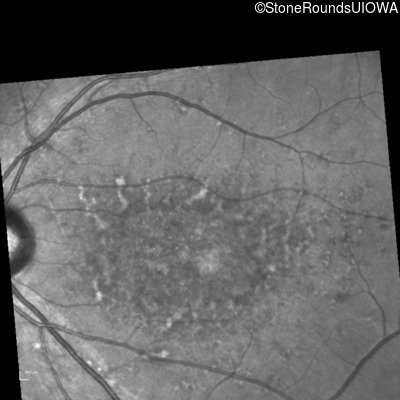

Infrared Fundus Photograph - Left - 20/150

Exemplar